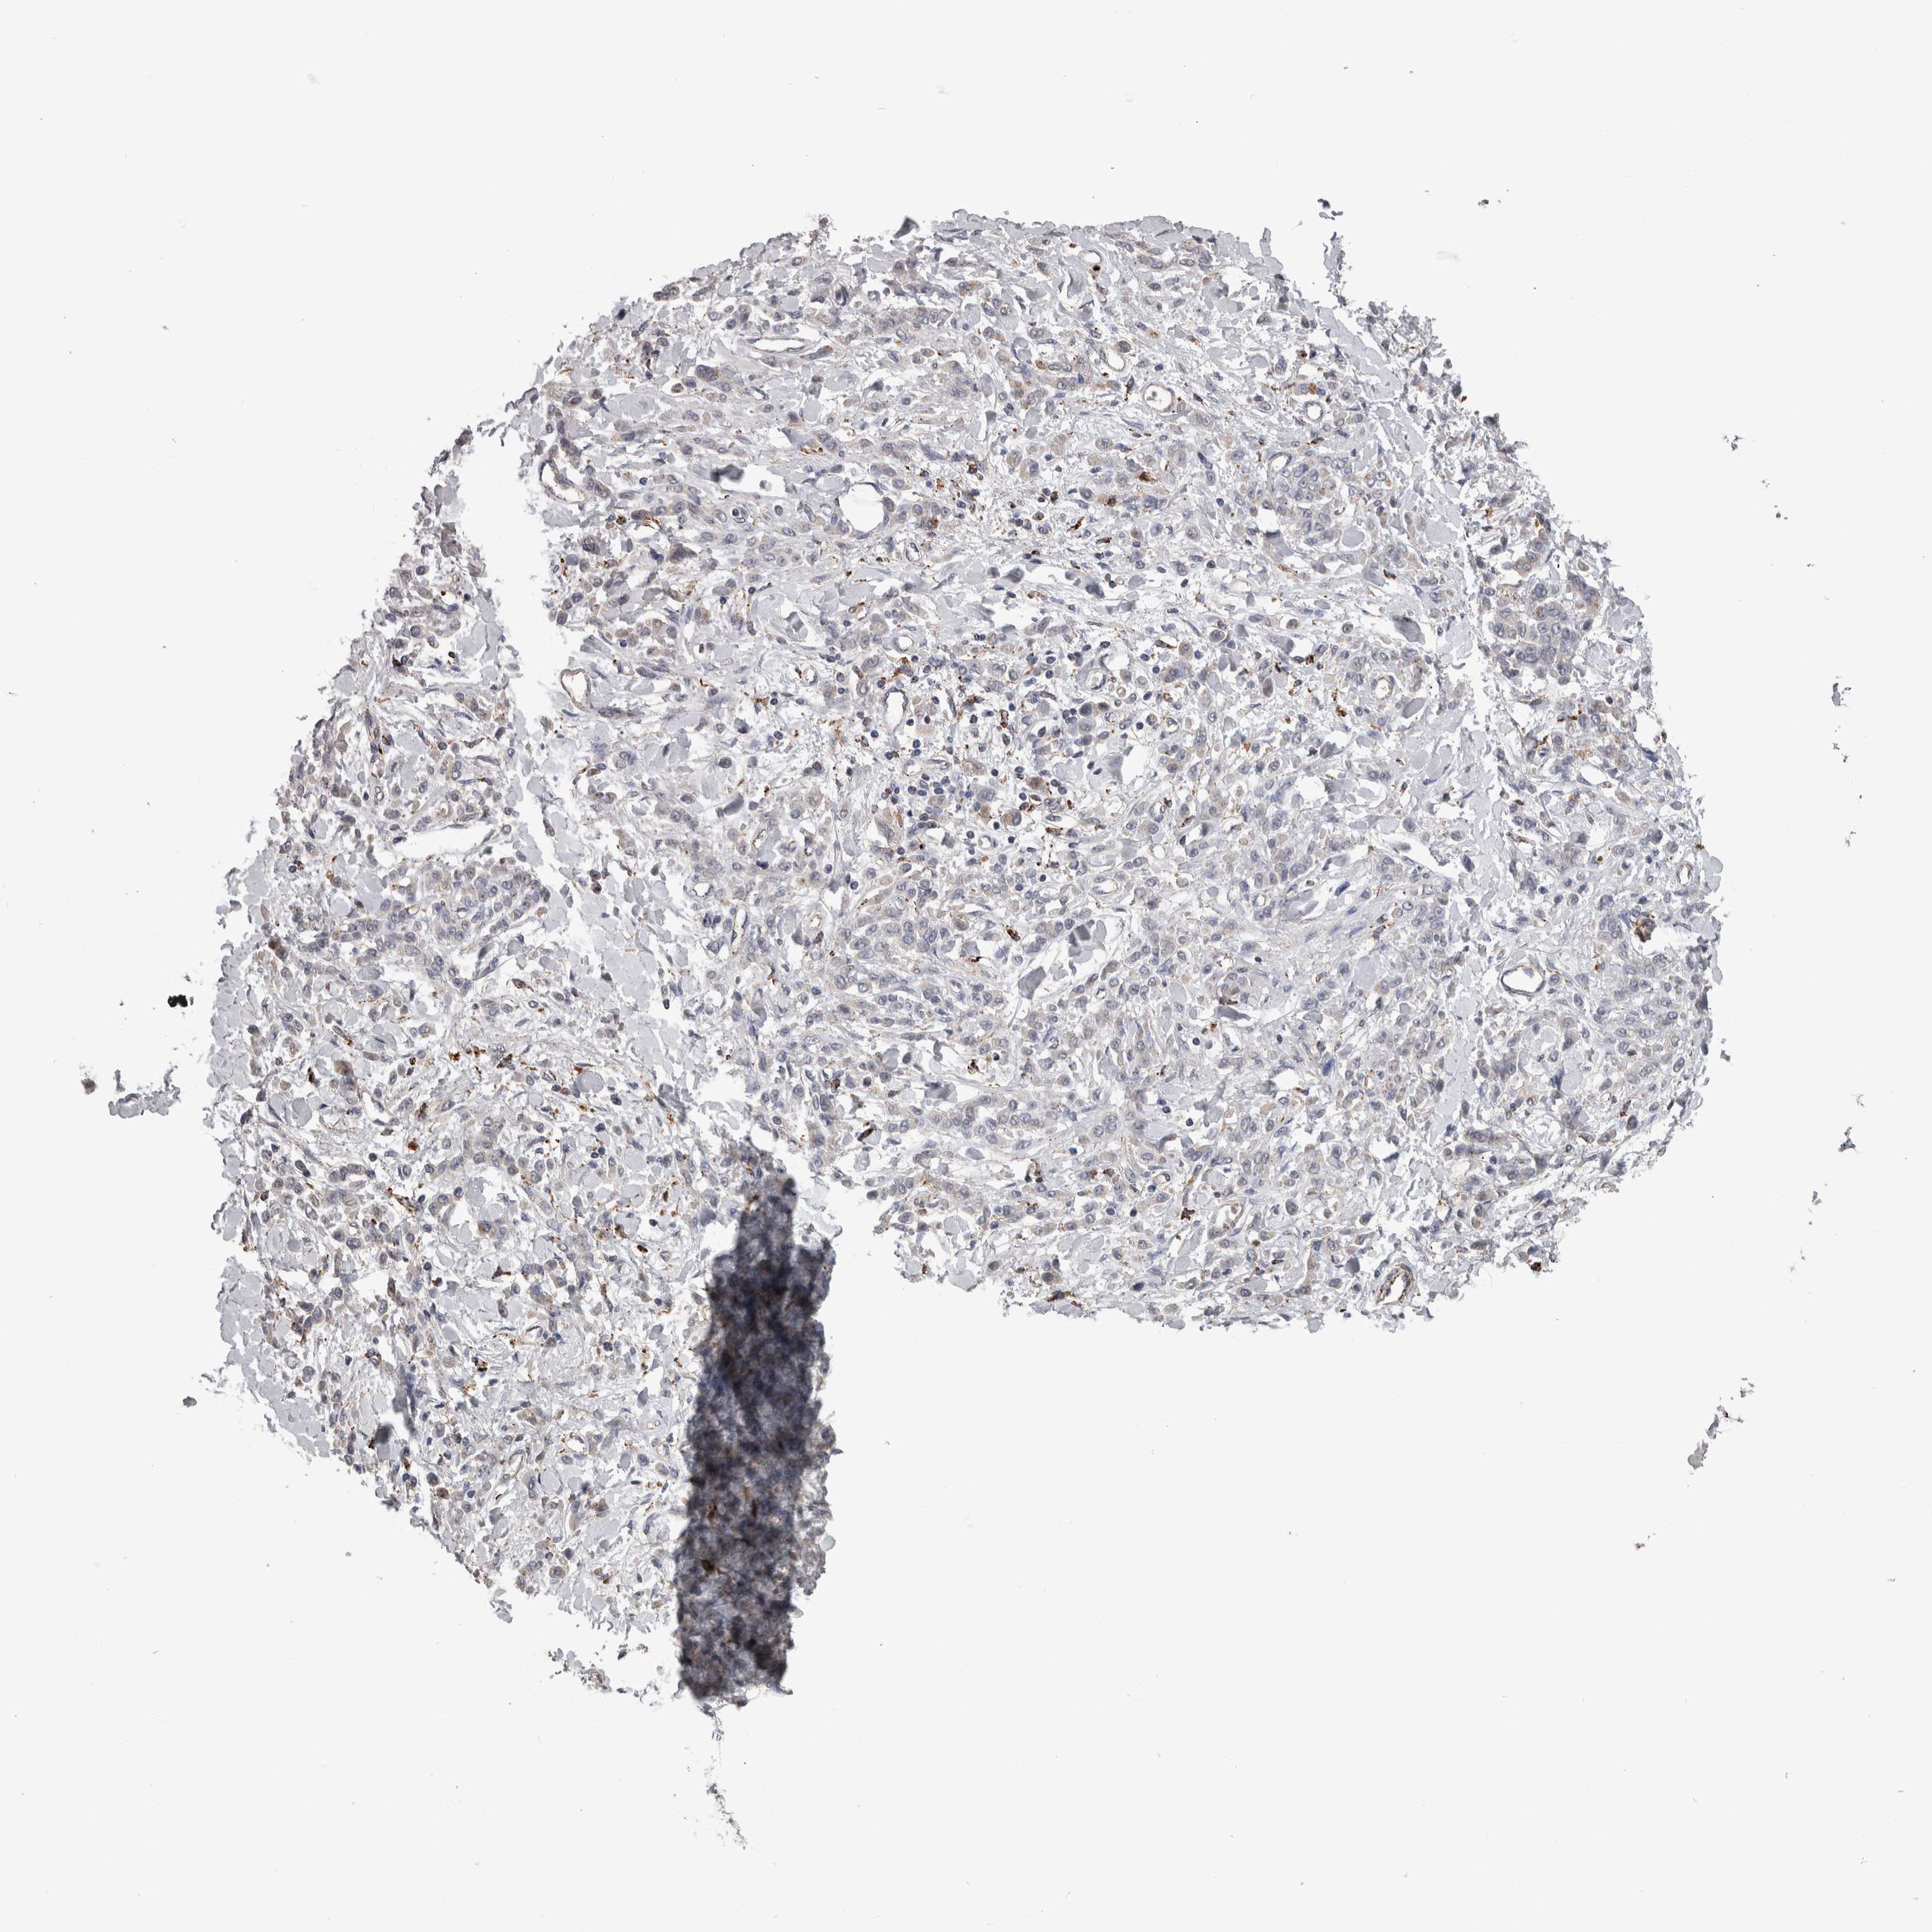

STOMACH CANCER - Protein expressioni

A mouse-over function shows sample information and annotation data. Click on an image to view it in a full screen mode. Samples can be filtered based on level of antibody staining by selecting one or several of the following categories: high, medium, low and not detected. The assay and annotation is described here.

Note that samples used for immunohistochemistry by the Human Protein Atlas do not correspond to samples in the TCGA dataset.

Antibody stainingi

Antibody staining in the annotated cell types in the current human tissue is reported as not detected, low, medium, or high, based on conventional immunohistochemistry profiling in selected tissues. This score is based on the combination of the staining intensity and fraction of stained cells.

Each image is clickable and will lead to virtual microscopy that enables deeper exploration of all samples and also displays staining intensity scores, fraction scores and subcellular localization as well as patient and tissue information for each sample.

Antibody HPA049876

Antibody HPA053504

Antibody CAB025114

Staining

High

Medium

Low

Not detected

Intensity

Strong

Moderate

Weak

Negative

Quantity

>75%

75%-25%

<25%

None

Location

Nuclear

Cytoplasmic/membranous

Cytoplasmic/membranous,nuclear

Adenocarcinoma, NOS